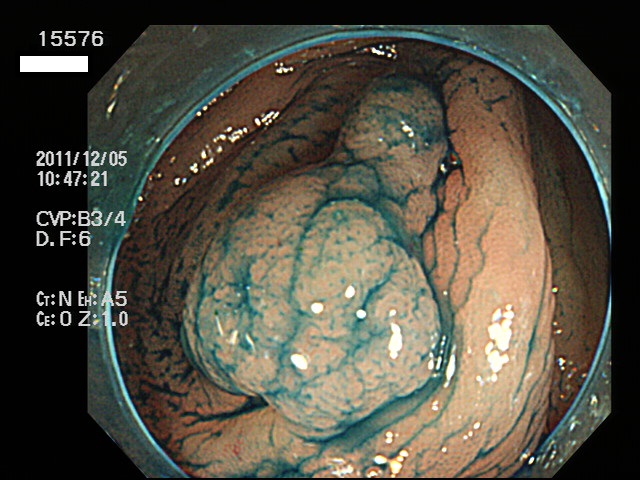

虫垂開口部の過形成ポリープ(SSAP)の例